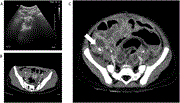

Aggressive angiomyxoma persistently misdiagnosed as an obturator hernia managed with resection and hormonal therapy: case report

Nawaf Abdulkareem Alomary and others

Journal of Surgical Case Reports, Volume 2020, Issue 9, September 2020, rjaa330, https://doi.org/10.1093/jscr/rjaa330